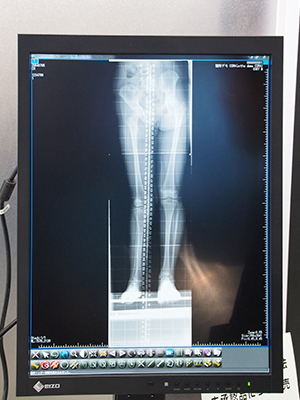

●豊富にインプラントのテンプレートを用意し,手術をサポートする整形外科向けPACSのiRad-OT

整形外科領域は,フィルム上で高度な計測を行うほか,長尺撮影などが多いために,フィルムレス運用に移行しにくかった。このような整形外科領域におけるフィルムレス化の課題を解決するPACSがiRad-OTである。整形外科の診療に特化してシステムとして開発されたiRad-OTは,Sharp角やFTA,Cobb角に加え,「線分上の任意の点からの垂線」といった高度な計測機能を搭載している。また,計測ツールを組み合わせた計測ガイドを作成して,ほかのユーザーと共有することも可能である。

このほか,インプラント手術向けに,主要メーカーのインプラントをテンプレートに登録しており,画像に重ね合わせて,シミュレーションを行える。このインプラントはメーカー別,部位別にリスト化され,新製品が出ると更新される。

整形外科向けPACSの「iRad-OT」 |

「iRad-OT」は,高度な計測ツールを搭載し, |